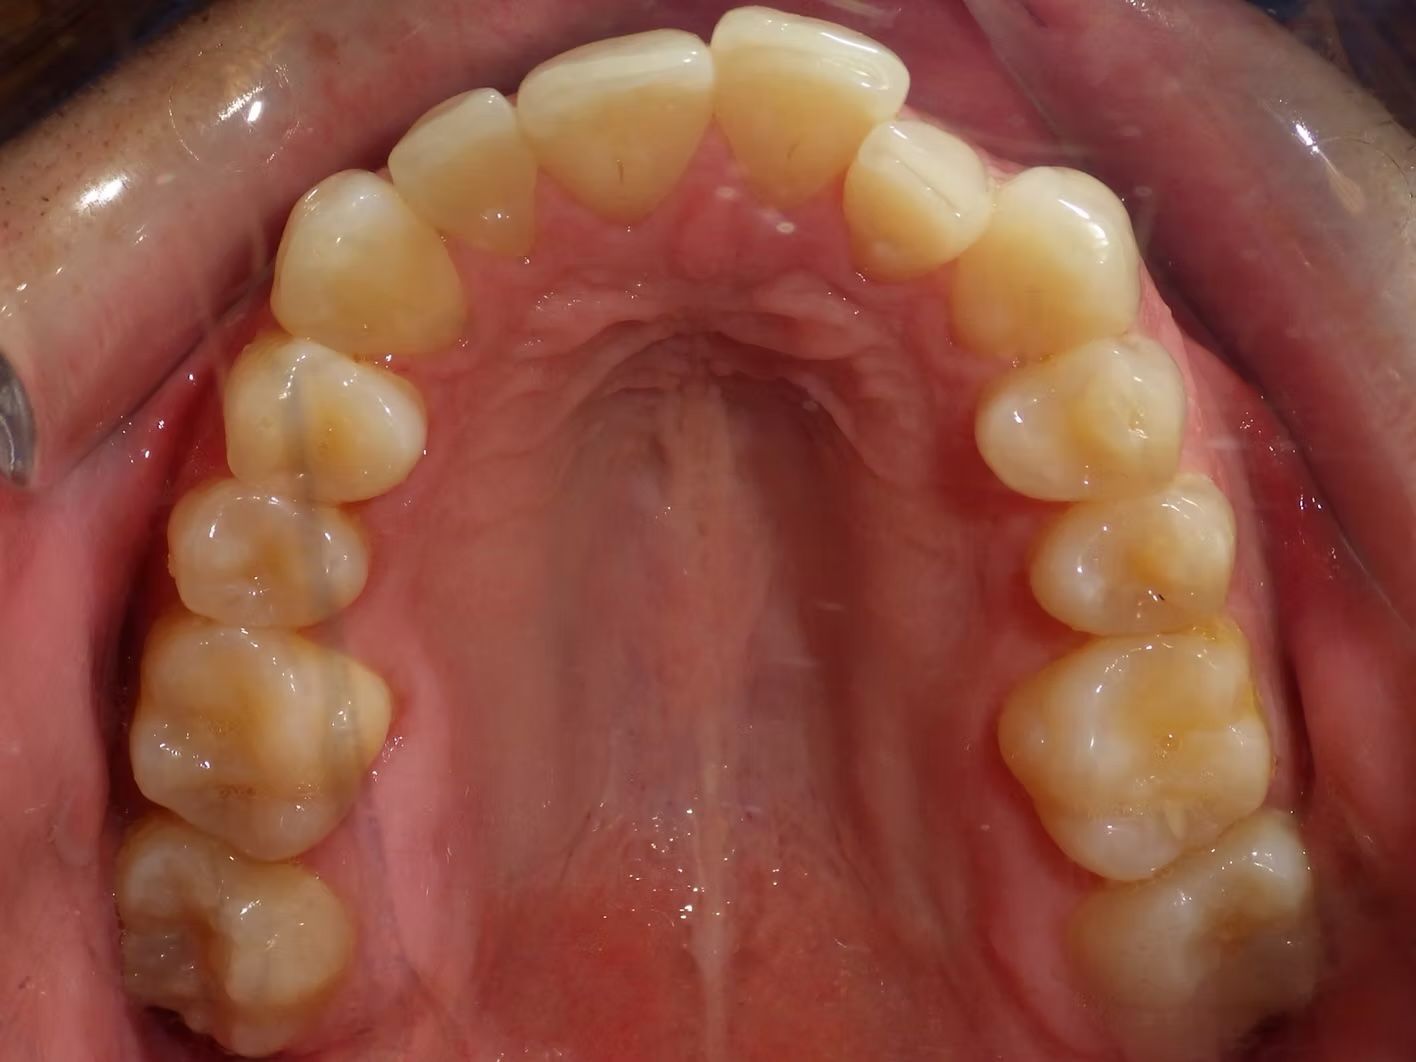

IAN

Ian came to the office because his lower teeth were crowded and he had an anterior cross bite. With traditional braces we resolved the crowding and aligned the teeth without causing flaring of the incisors and giving him a handsome smile. The treatment lasted 18 months and the final photos are at a 2 year follow up when we made him a new clear retainer.